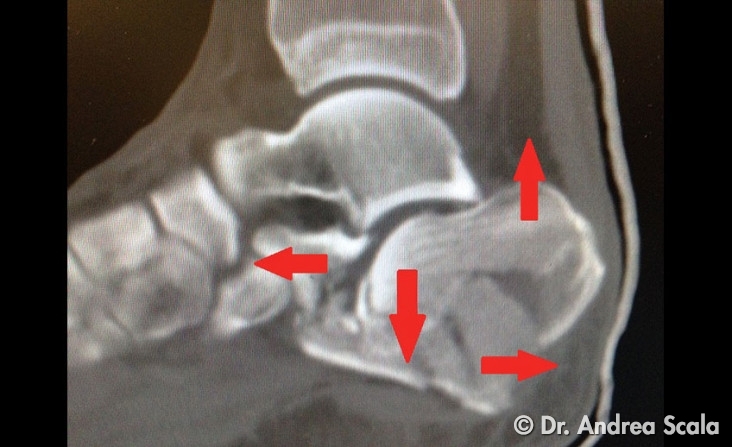

Queste immagini TAC, contrassegnate dalle frecce rosse, fanno capire in quanti frammenti si è rotto il calcagno di questo motociclista.